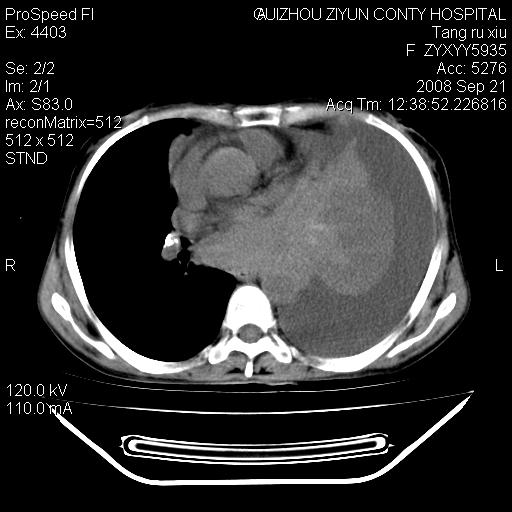

f、57岁,上腹痛.2月,近来胸闷。2月前在外院摄胸片示左侧胸腔少量积液。

(患者腹痛入院,欲吐,临床医生说禁饮,所以没有口服对比剂)

考虑----左侧胸腹腔积液----压迫性肺不张----心包积液---肝脏多发低密度影-----穿刺抽液后复查

左侧胸壁见一结节影,肝脏多发低密度影,左侧胸腔大量积液。建议增强

1)考虑左侧肺癌侵犯纵隔,左侧胸膜、肝脏及腹膜后淋巴结转移。2)左侧胸腔积液。3)心包积液。

肝脏大小形态尚可,其实质内可见多发大小不等的低密度影,边缘模糊。肝门区结构紊乱,腔静脉腹主动脉旁可见多发软组织密度影,部分融合成团块状,并向下延伸。胰腺及十二指肠结构显示不清。腹腔内脐后肠管走形僵硬,管壁可见增厚。盆腔内可见多个淋巴结影。所扫层面左侧胸腔可见大量弧形水样密度影,其内侧可见被压缩的肺组织影。左侧胸壁可见一小结节样软组织密度影,边缘模糊。心脏纵隔向右侧移位。心脏包膜内可见囊样低密度影,其内侧心房室周围可见一圈气体样密度影。纵隔内大血管旁可见多发软组织团块影,部分融合。

1.腹膜后淋巴瘤侵及肝脏,肺内及纵隔内多发转移。2.左侧大量胸腔积液并压缩性肺不张。3.心包脓肿可能,转移不除外。4.脐后局部肠管管壁增厚,考虑炎症可能,肿瘤不除外。